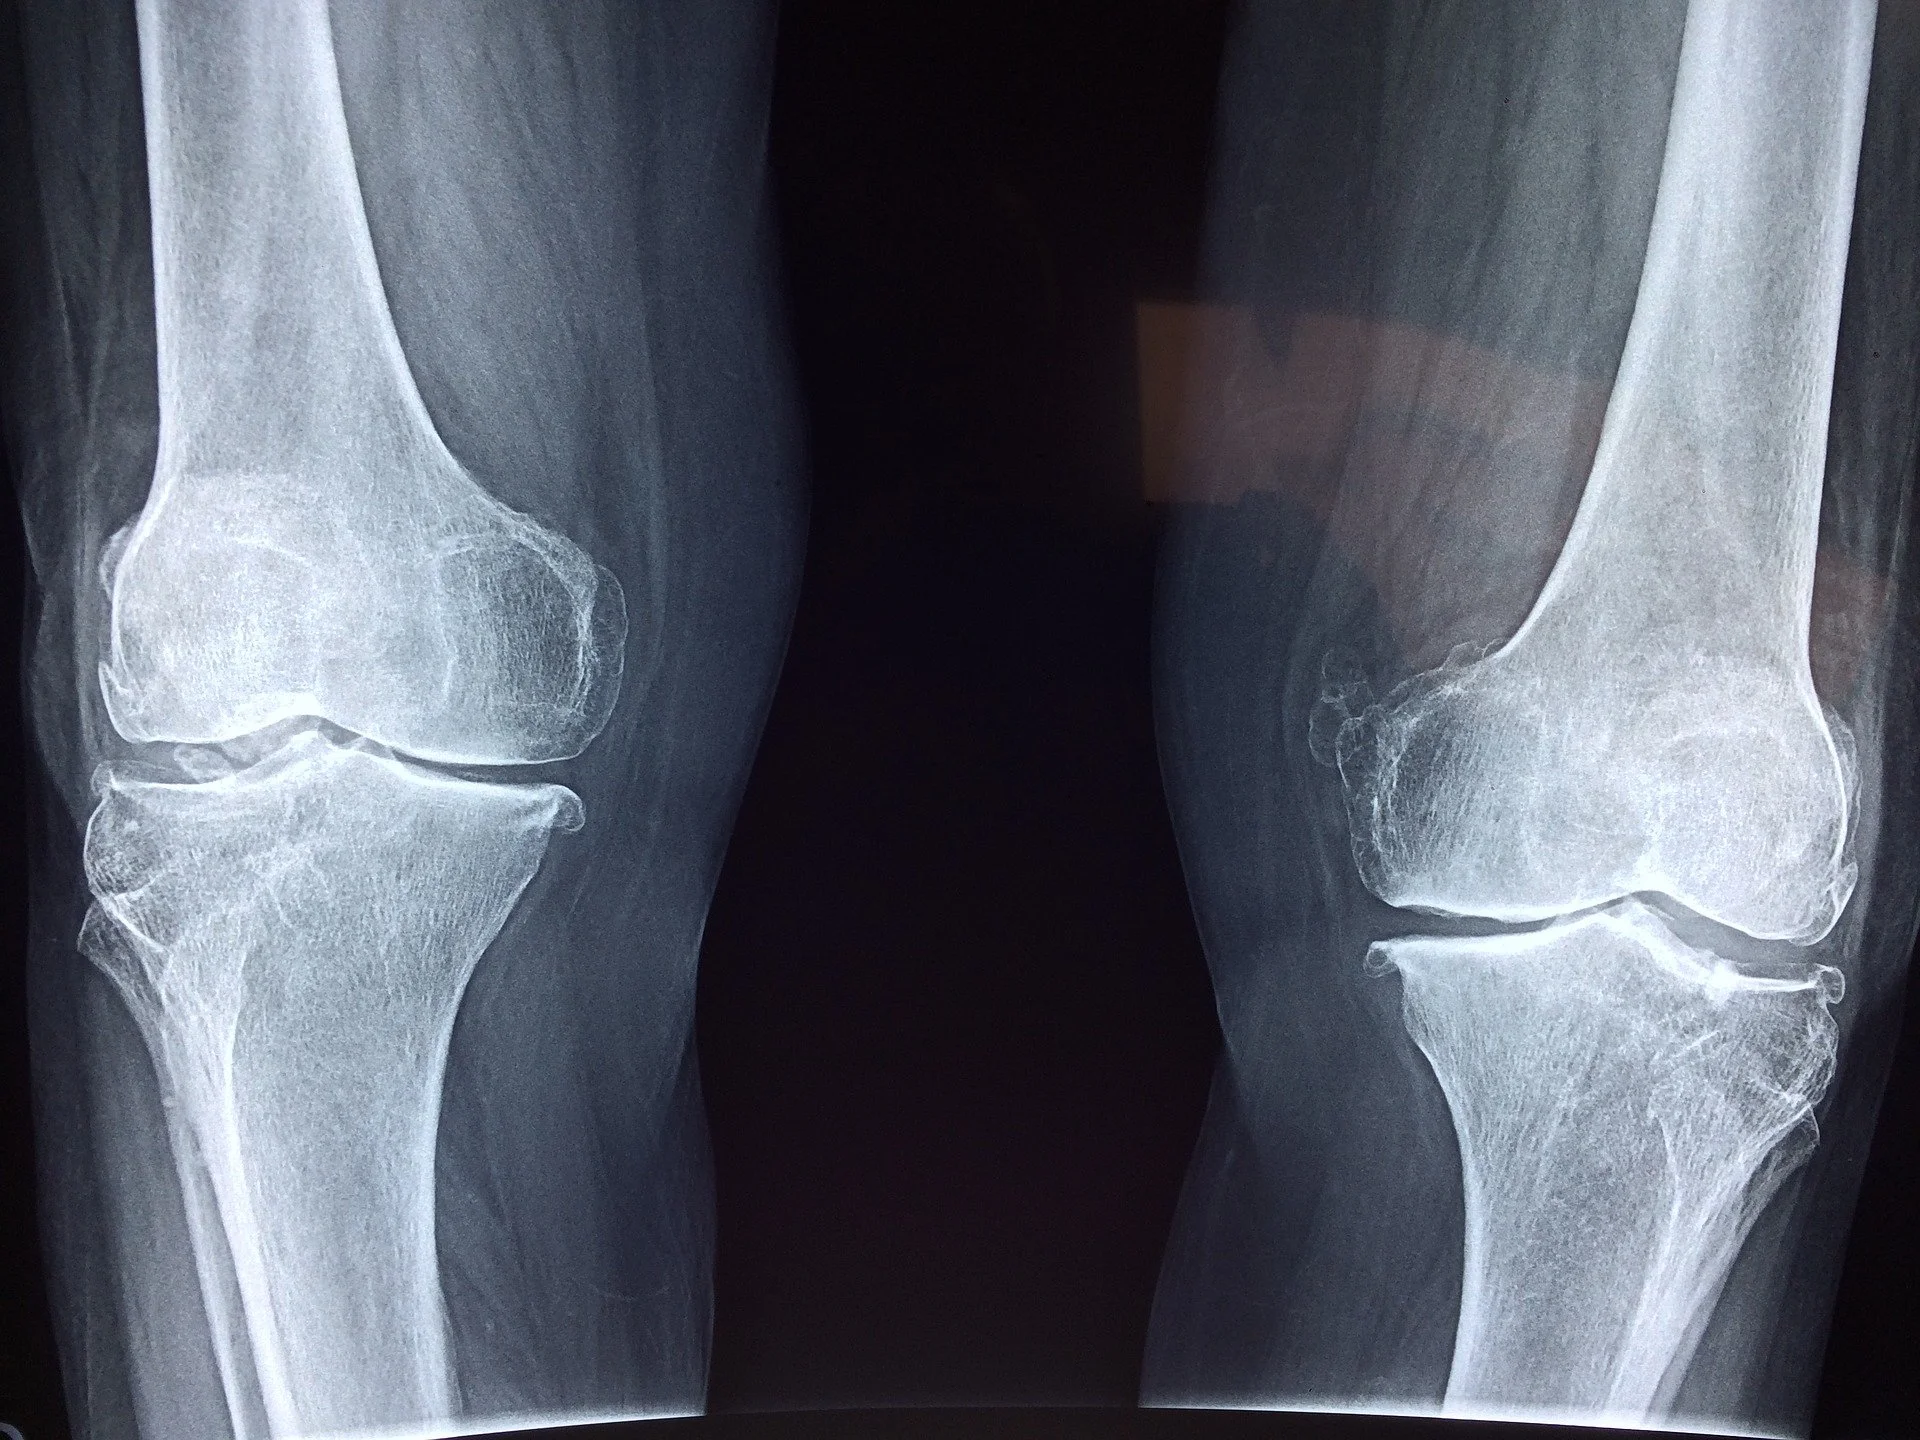

What are the most effective treatments for osteoarthritis?

The reality is that OA is a chronic and progressive degenerative joint disease characterized by the breakdown of cartilage and changes in bone structure. Non-operative conservative management options aim to reduce pain, improve function, and enhance the quality of life for those affected.

While we can’t turn back time and reverse the degenerative changes that have occurred in a joint with OA, treatments and rehabilitation can certainly slow down, and in some cases even halt, that progression.

Everything you ever wanted to know about conservative management of osteoarthritis and more